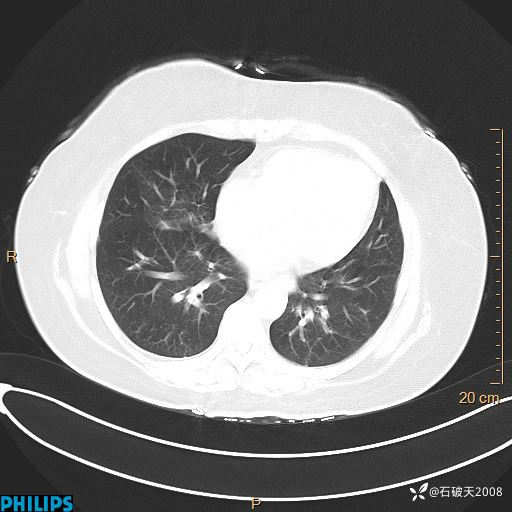

肺结节病?纵膈型肺癌?淋巴瘤?有点意思,欢迎围观

女 52岁 主 诉:咳嗽10余天,咳痰2天。

现病史:10余天前无明显诱因出现咳嗽,呈阵发性干咳,伴咽喉部发痒,无咽痛,无咳痰,无鼻塞、流涕、打喷嚏,无发热、畏寒、寒颤,无头痛、头晕,无胸闷、胸痛,无反酸、烧心,无腹痛、腹泻,无尿频、尿急,无皮疹等,在当地诊所求治,给予口服药物治疗(具体不详),病情无好转。遂在当地社区卫生服务中心开具口服药物治疗(具体不详),疗效欠佳。2天前出现咳痰,在我院门诊求治,行胸部CT提示肺部感染,建议住院,患者要求口服药物治疗,目前仍咳嗽、咳白色粘痰,白天量多,夜间自觉喉部喘鸣音,遂再次来院就诊,以“肺部感染”为诊断收入院。发病以来,神志清,精神可,饮食可,夜间睡眠差,大小便正常,近期体重无明显变化。

肺窗